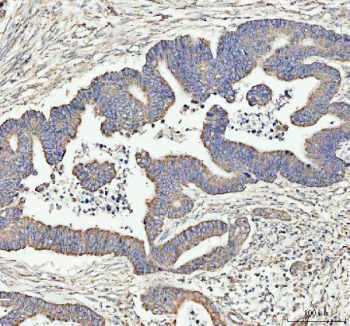

Immunohistochemical staining of ARHGEF12L using anti-ARHGEF12L antibody. ARHGEF12L was detected in a paraffin-embedded section of human colorectal adenocarcinoma tissue. Heat mediated antigen retrieval was performed in EDTA buffer (pH 8.0, epitope retrieval solution). The tissue section was blocked with 10% goat serum. The tissue section was then incubated with 2 ug/ml rabbit anti-ARHGEF12L antibody overnight at 4oC. Peroxidase Conjugated Goat Anti-rabbit IgG was used as secondary antibody and incubated for 30 minutes at 37oC. The tissue section was developed using an HRP secondary and DAB substrate.